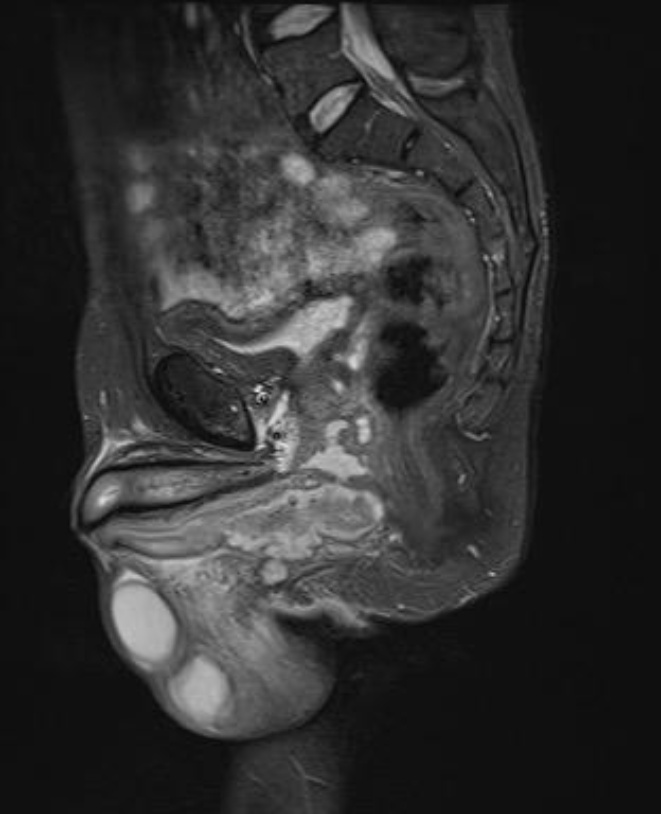

• 3) Imaging: Ultrasound revealed a thickened, edematous scrotal sac with a loculated collection (35 × 10 mm) at the posterolateral aspect, suggestive of cellulitis and abscess formation [3]. MRI confirmed an irregular fluid collection within the corpus spongiosum at the level of the superior pubic ramus, extending to the prostatic urethra with intense enhancement of the soft tissues [4]. Figures 1-3 show the pre operative MRI.

Figure 2. Sagittal T2-FS weighted MRI showing extension of the periurethral abscess along the proximal corpus spongiosum without evidence of cavernosal involvement.